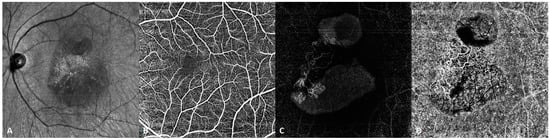

Figure 7.

SS-OCTA image of a patient with polypoidal choroidal vasculopathy. (A) Infrared fundus image. (B) Normal retinal superficial vascular network. (C) SS-OCTA demonstrating choroidal neovascularization and a polypoidal lesion under the elevated pigment epithelial detachment (PED) in the avascular layer of the retina. (D) The choriocapillaris exhibits a branching neovascular network. SS-OCT clearly reveals the vascular structure within the PED, which was barely revealed using SD-OCT.